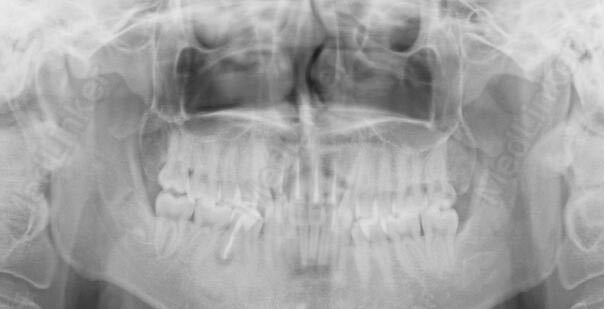

右侧下颌第二前磨牙根尖周炎

右侧下颌第二前磨牙叩痛,松动度可。余未见异常。曲面断层片提示右侧下颌第二前磨牙根尖密度减低,髓腔内可见根充物质,

RCT治疗后根尖区密度增高,恢复良好。